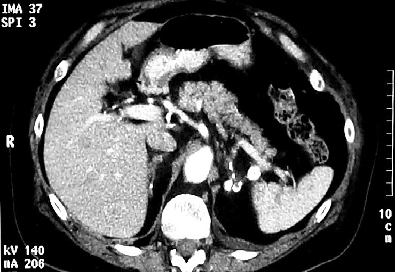

4. التصوير: يمكن أن يطلب الطبيب من المريض إجراء تصوير مقطعي محوسب للبطن (CT scan) لمعرفة حجم الغدد الكظرية والبحث عن شذوذات أخرى يمكن أن تكون سبباً في حدوث القصور الكظري. كما يمكن أن يقترح الطبيب إجراء مسح بالرنين المغناطيسي للغدة النخامية في حال أشار الفحص لوجود قصور كظري ثانوي.